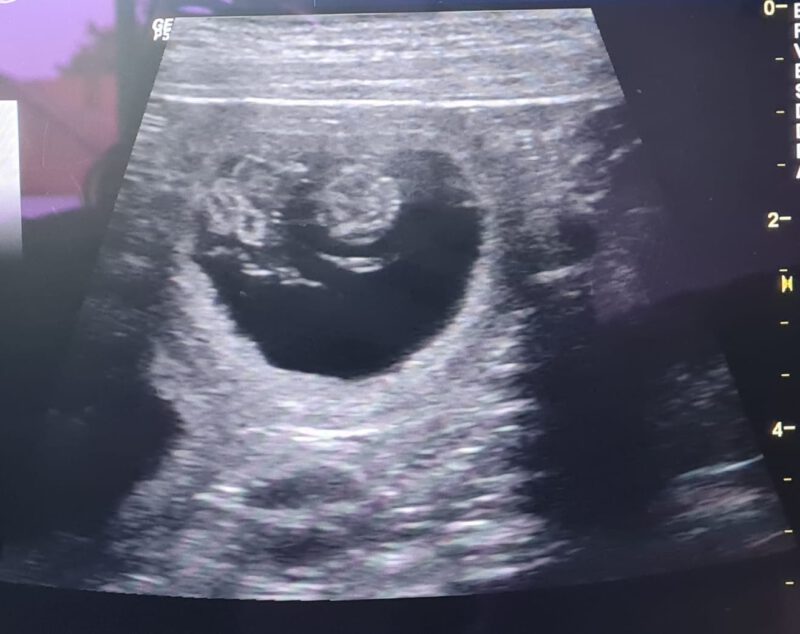

33.Tag – Fruchtampullen wachsen zusammen

Die Gebärmutter zeigt zunächst oviole Fruchtampullen , die um den 33. bis 35. Tag ”zusammenfließen” und zu Schläuchen auswachsen. Die Gebärmutter faltet sich, da der Platzbedarf der Welpen enorm ist. Achtung! Um den 35. Tag ist die Organogenese (Organbildung) bei den Welpen abgeschlossen. Bis dahin sind die Welpen äußerst empfindlich für äußere Einwirkungen wie Medikamente…